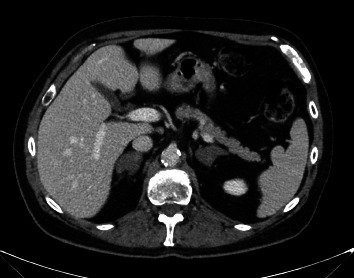

We report a case of successfully lateralized adrenal cortisol hypersecretion by adrenal venous sampling (AVS) and improved by surgery. AVS is a commonly used tool to guide surgical management of primary hyperaldosteronism. It can determine lateralization, leading to unilateral adrenalectomies of the correct side, or nonlateralization, which precludes surgery. The use of AVS in determining lateralization in hypercortisolism is a growing field of discussion. Currently, there is no defined or unanimous protocol behind procedural details and interpretation of results. In this report, we describe the AVS protocol at our institution for hypercortisolism, interpretation of the results, and corresponding surgical outcomes for a case of mild autonomous cortisol secretion.

Abstract Image